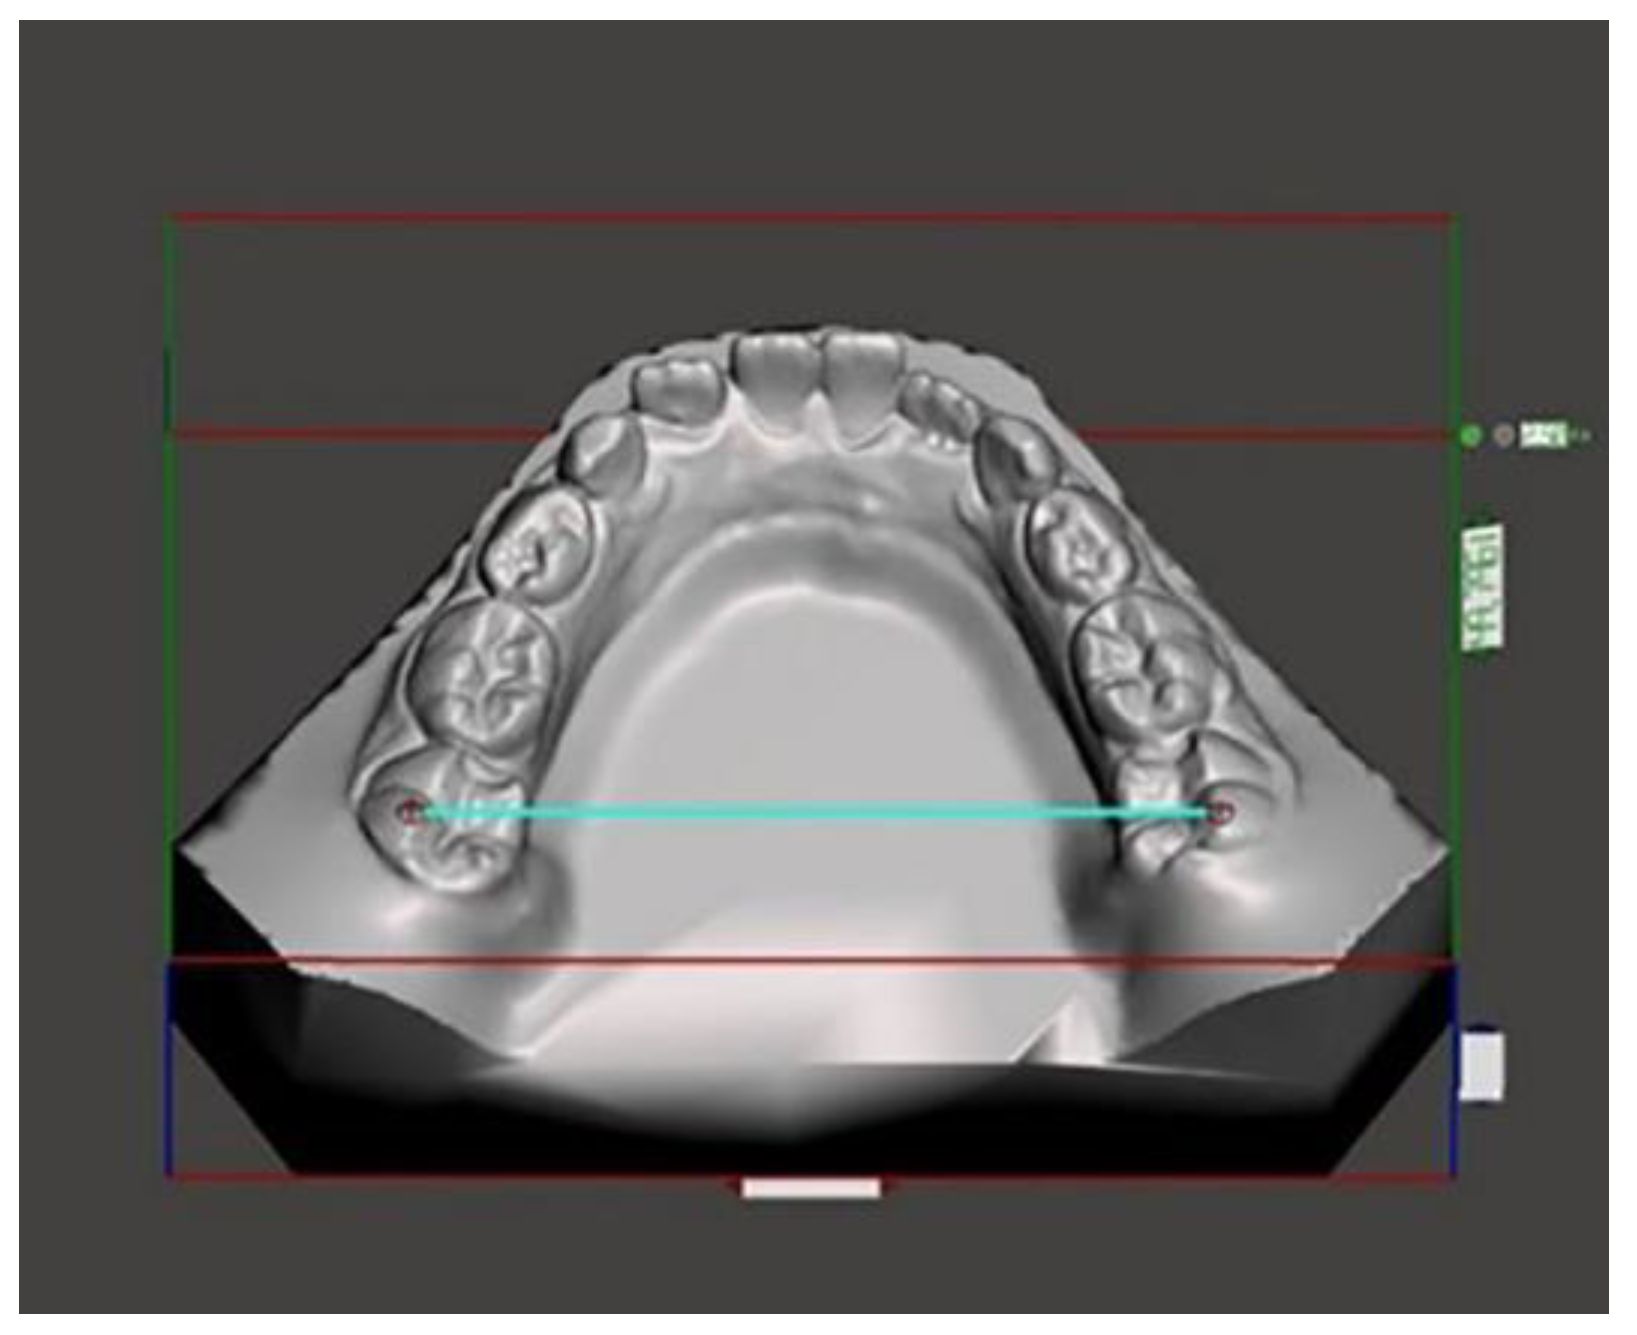

Figure 5.

Intermolar angle.